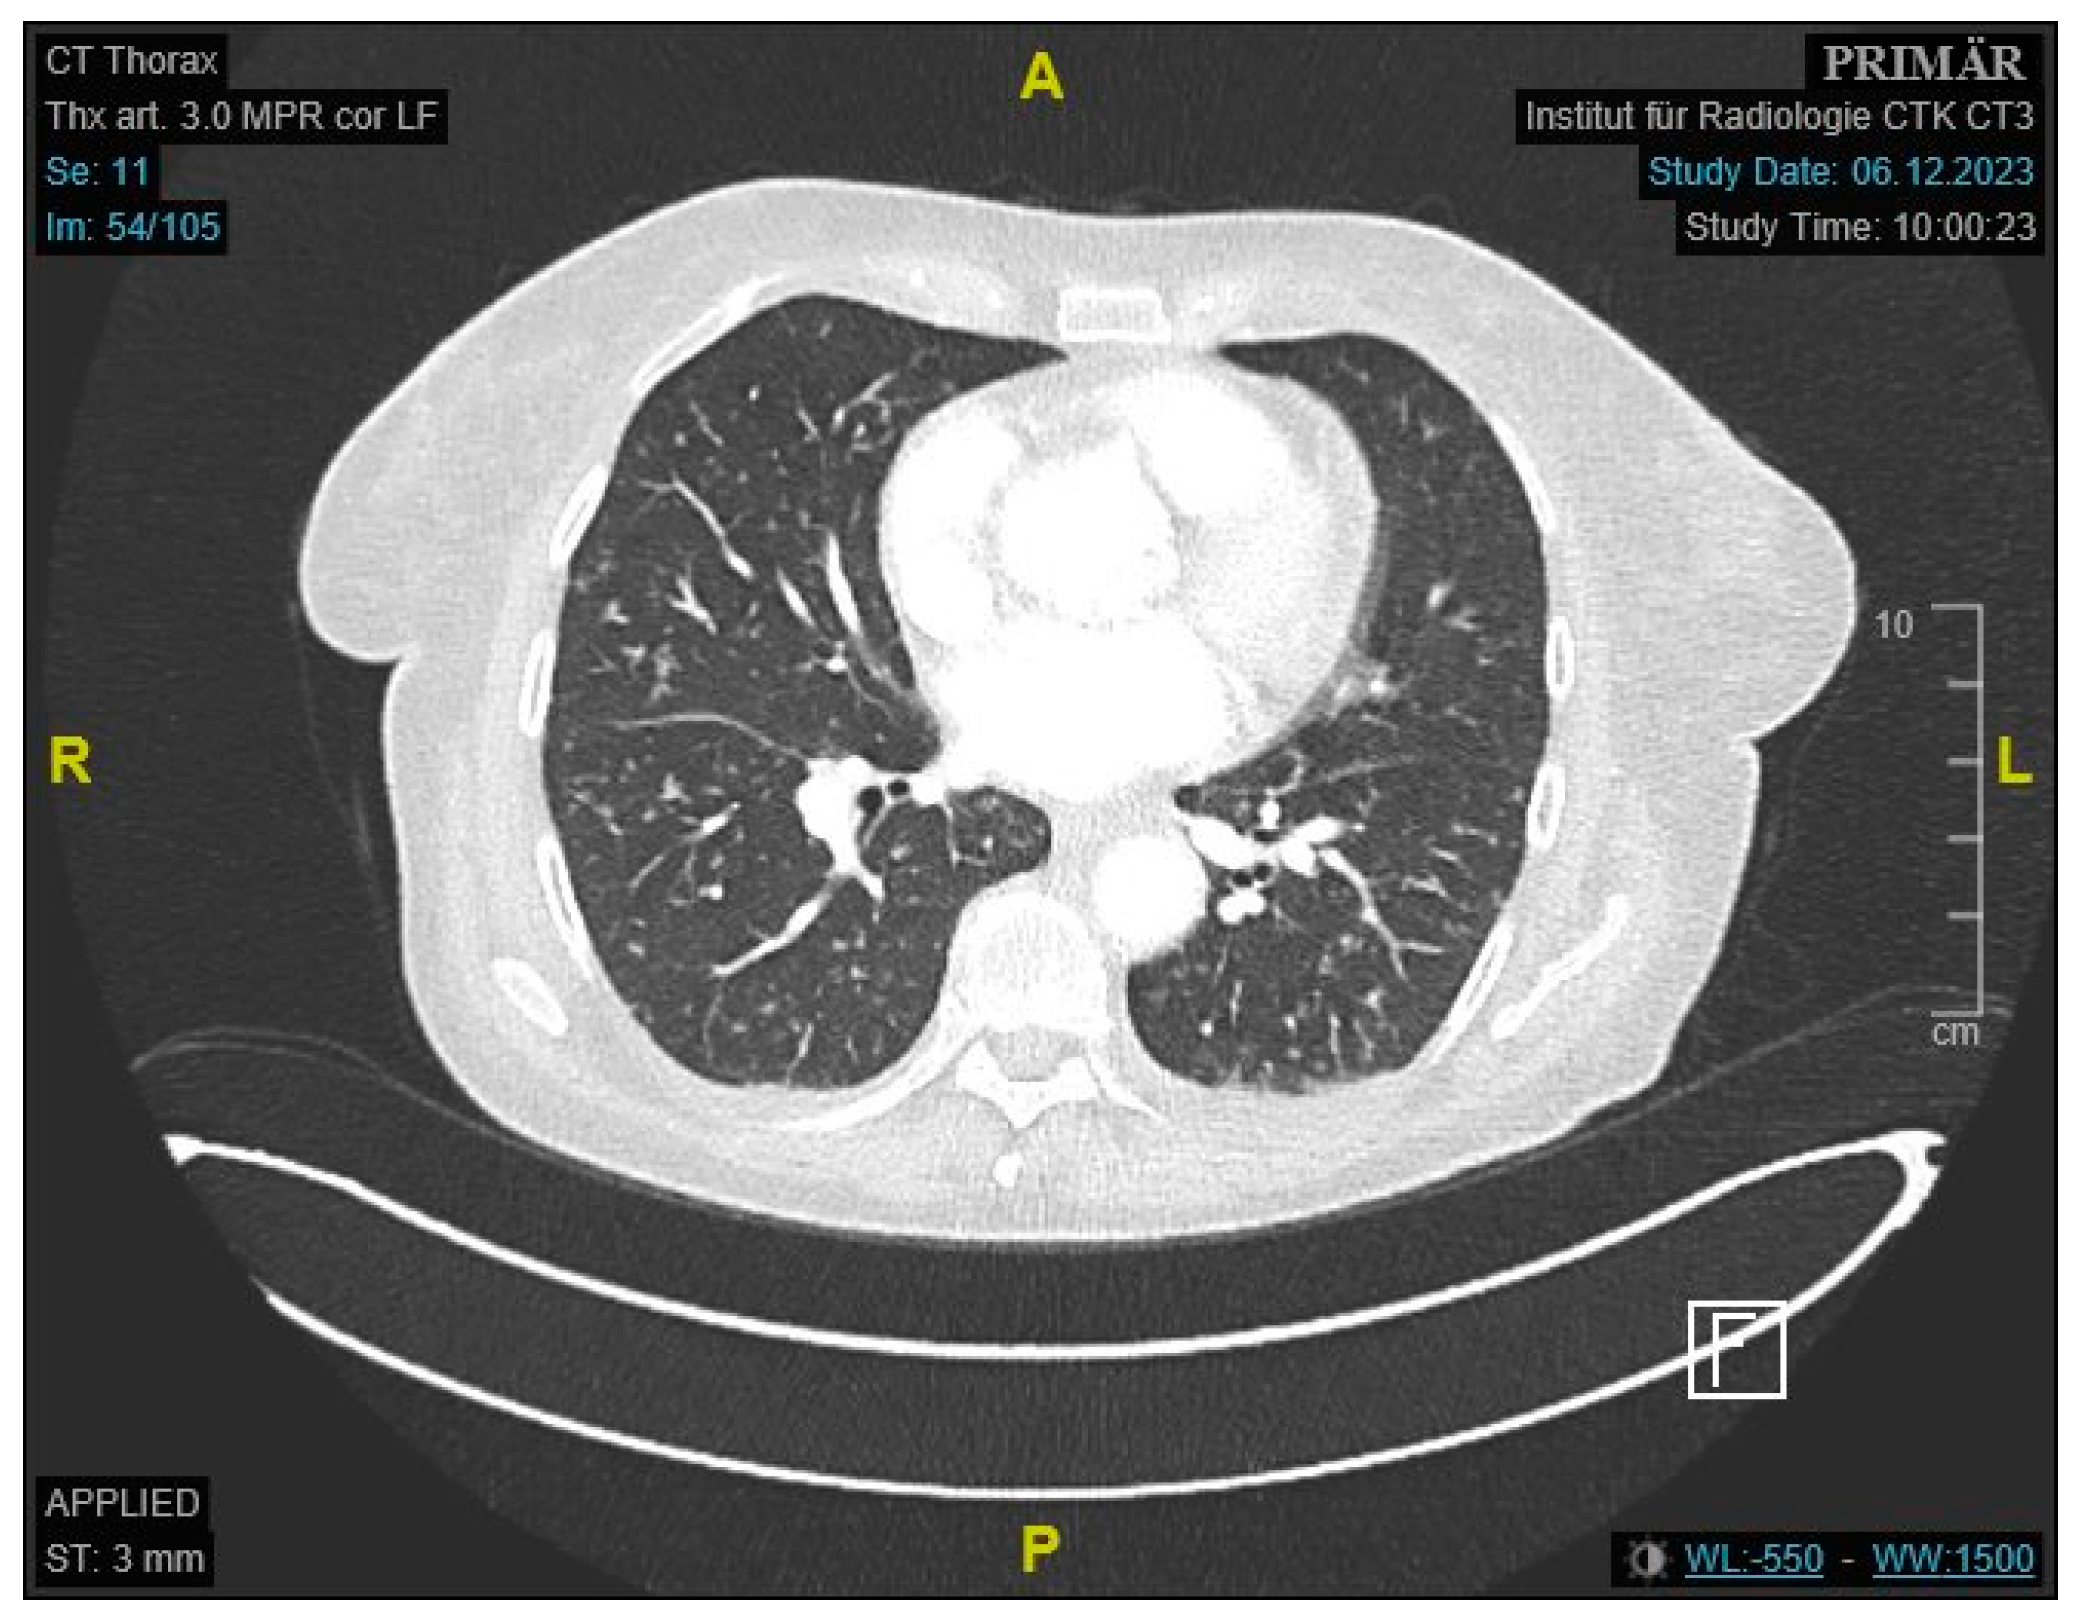

Initial labs showed microcytic anemia with suspicion of iron deficiency. Abdominal ultrasound showed marked ascites and findings suggestive of peritoneal carcinomatosis. A CT of the abdomen revealed a small bowel conglomerate tumor (Figure 1) and enlarged paraaortic lymph nodes. Chest CT demonstrated bilateral scattered consolidations suspicious for metastatic spread (Figure 2). Bronchoscopy was unremarkable, and direct microscopy was negative for AFB. Subsequently, the patient developed a small bowel ileus, raising suspicion for a jejunal tumor. During the subsequent emergent laparoscopy, we observed a conglomeration tumor consisting of the loops of the small intestine. Emergency laparoscopy revealed a small bowel conglomerate mass, and the biopsy from the lower abdomen showed caseating granulomatous peritonitis (Figure 3). A detailed history revealed her partner had previously been diagnosed with pulmonary tuberculosis caused by Mycobacterium chimaera. The patient had no follow-up for TB because her partner was considered not infectious.

Figure 2. Contrast-enhanced CT of the thorax showing scattered pulmonary consolidations.

The presented cases highlight the diagnostic complexity of abdominal TB in patients with nonspecific GI and systemic symptoms. In the first case, we initially suspected a gastrointestinal infection; however, imaging revealed a small bowel mass and pulmonary lesions, leading to a working diagnosis of metastatic GI malignancy. Approximately one-third of small intestinal cancers present with metastases, frequently involving the lungs [26,27]. Symptoms are often vague and may include GI bleeding and abdominal tenderness [28]. However, endoscopically obtained samples in our patient showed no malignant epithelial transformation.